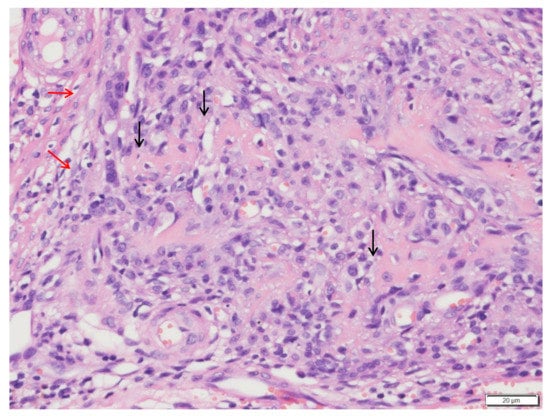

:1. Case Description

2. Materials and Methods

3. Results